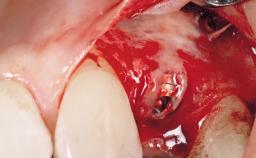

A 29-year-old female patient presented for treatment to replace the upper left central incisor tooth with an implant- supported restoration. The tooth had been intermittently symptomatic for the previous 12 months. The tooth had originally suffered trauma about 15 years previously. Several endodontic treatments had been performed, including an apicectomy procedure to retain the tooth. The patient was healthy and a non-smoker. She had reasonable expectations in regard to esthetic outcomes and the risk of marginal tissue recession following treatment. At medium smile, the gingival margins of the upper teeth were visible, with a display of 3 to 4 mm of the gingival margins. Gingival recession of tooth 21 and a discrepancy in the gingival levels between teeth 11 and 21 was observable during normal speech and smile.

| Placement Protocol | Immediate implant placement |

| Socket Integrity | Damage to one or more bone walls |

| Bone Volume | Damage to one or more socket walls |